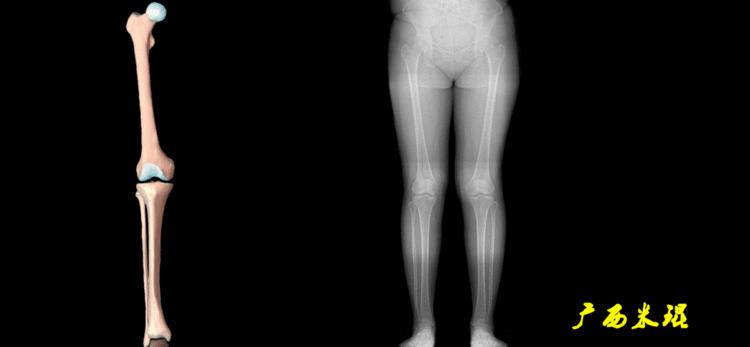

站立侧位(矢状面)股骨头中心与踝关节中心的连线也通过膝关节中心,这也是下肢的机械轴线,这也是下肢力线。

矢状面的下肢力线常常被医生忽视,其实它的改变也是膝关节疼痛的常见原因。

我们说了这么多照片的下肢力线测量,体表也是可以粗略测量的,自股骨头中心至踝关节中心拉一直线,髌骨中心点位于此直线上;自髂前上棘至踝关节中心拉一直线,髌骨中心点位于此直线内侧;自髂前上棘至第1、2趾间拉一直线,髌骨中心点位于或接近此直线。

(3)垂直轴

也就是下肢的负重轴,它是身体的纵轴线,与地面垂直,由于双髋比双踝的距离宽,所以垂直轴与下肢力线(机械轴)存在3°的外翻。